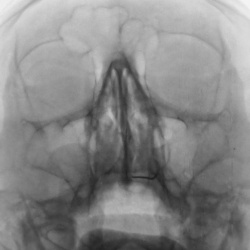

Какие мнения будут по поводу снимка ППН?

Пациент направлен на рентгенографию ППН

Пациент направлен на рентгенографию ППН

Пациент направлен на рентгенографию ППН отоларингологом

Мужчина 1944 г.р. Направлен на рентгенографию ОНП для профилактики, перед операцией на глазах.Что с левой верхнечелюстной пазухой?